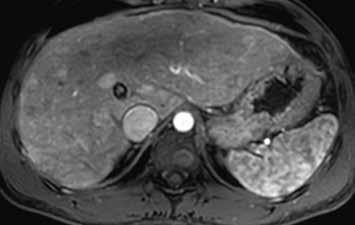

Na CEUS je v arteriální fázi patrný v levé polovině obrázku typický centrifugální charakter sycení ložiska, které je vidět v pravé polovině obrázku v B -módu (jako hypoechogenní) (6–8). Na CT (9) i MR (10) se ložisko (z obr. 4, 5) sytí homogenně, vyjma centrální vazivové jizvy, která zůstává hypodenzní.

V portovenózní fázi je ložisko izodenzní na CT (11), respektive izointenzní na MR (12).

V pozdní fázi je charakter ložiska stejný a nedochází k jeho vymývání ani na CT (13), ani na MR (14).

V centrální části ložiska je patrná vazivová jizva, která zůstává v arteriální fázi hypodenzní (9) a sytí se v pozdní fázi, kde je oproti zbytku ložiska hyperdenzní (13). Na MR je v T1-váženém obraze vazivová jizva hypointenzní (15), v T2-váženém obraze hyperintenzní (16).